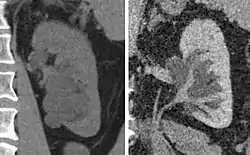

The presence of measurable contrast enhancement of the lesion is the most important characteristic in distinguishing between high-risk cysts (classifications III and IV) from the typically benign, low-risk Bosniak I, II, and IIF cysts.[8] Such contrast enhancement should be at least 10 to 15 Hounsfield units higher when compared with unenhanced images.

The complex cyst can be further evaluated with doppler ultrasonography, and for Bosniak classification and follow-up of complex cysts, either contrast-enhanced ultrasound (CEUS) or contrast CT is used.[12]